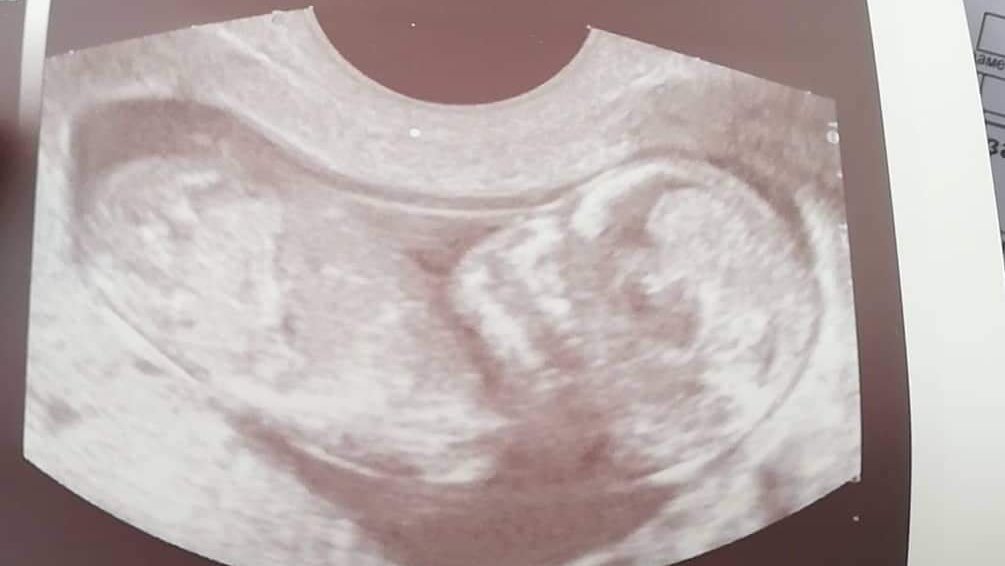

Феталната морфология е специализиран ултразвуков преглед, който се провежда между 18-та и 22-ра седмица от бременността. Той има за цел да оцени развитието на бебето и да идентифицира всякакви аномалии. По време на прегледа се изследва подробно анатомията на бебето, включително черепа, лицето, сърцето, крайниците, корема и гениталиите. Прегледът се извършва с помощта на ултразвукова машина, поставена върху корема на бременната жена. Продължителността му е приблизително 30 минути и помага за оценка на здравето и развитието на бебето по време на бременност.